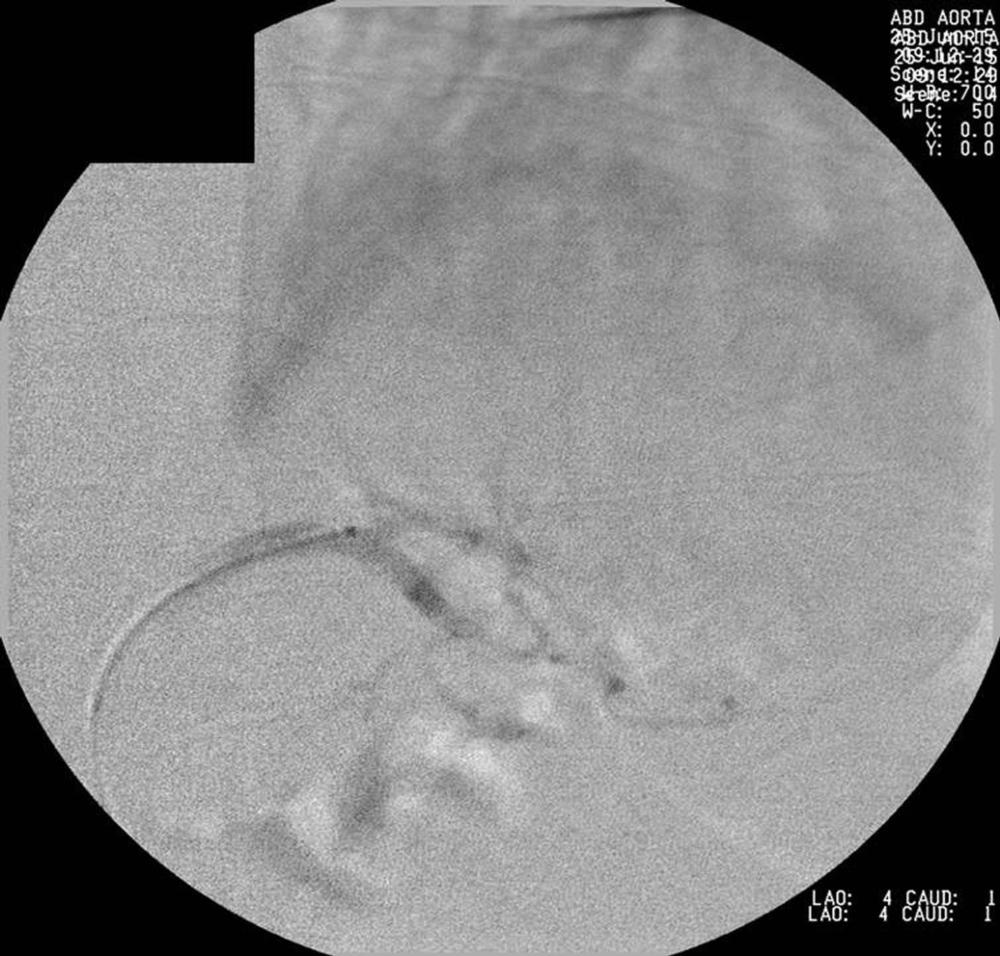

Figure 2. Left gastric artery prior to gastric artery embolization.

High-res (TIF) version

Figure 3. Left gastric artery prior to gastric artery embolization.